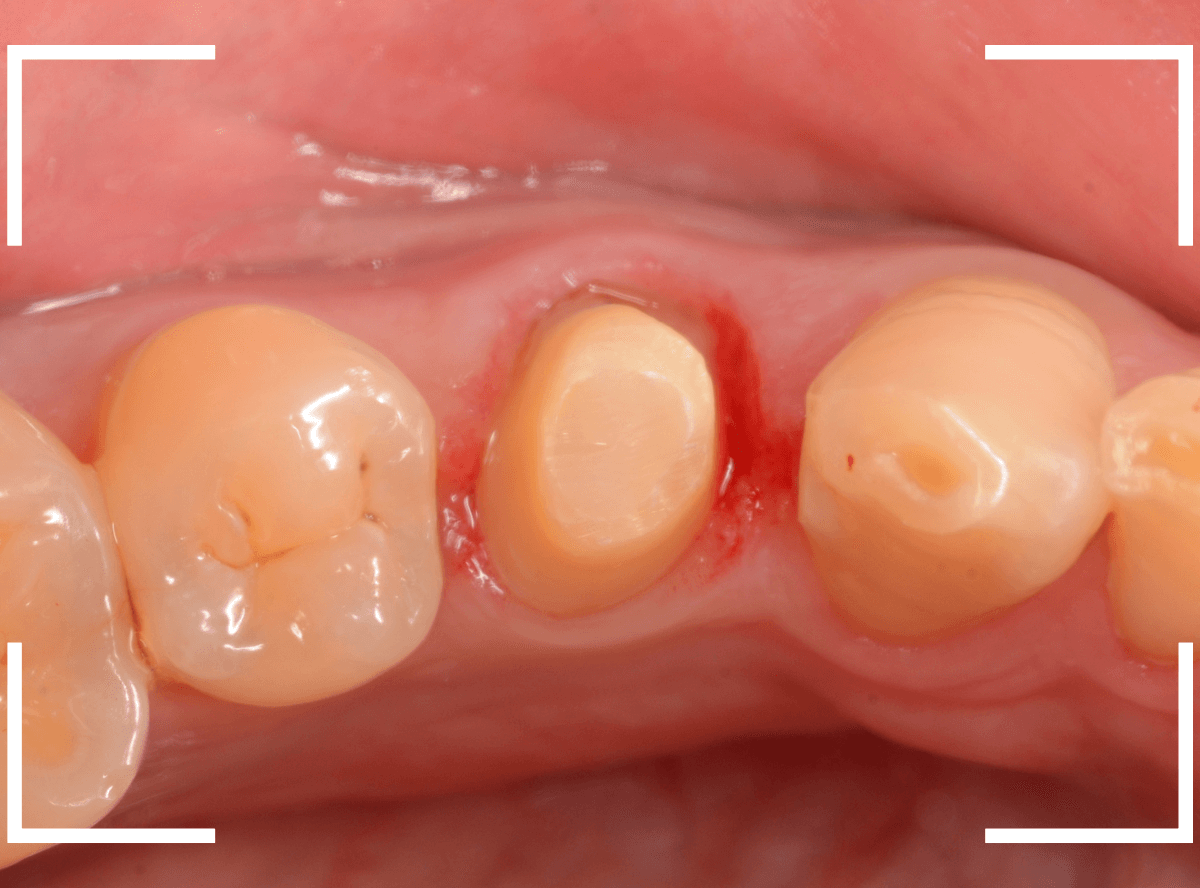

患者さんに状況を説明し、歯の周りの歯肉を麻酔をして電気メスでトリミングします。

このように歯の際が歯肉からしっかり出てる状況で製作しないと、さし歯はしっかりお口の中で安定しません。

この状態で新しい土台(ファイバー・コア)の型を取ります。

模型上でファイバーコアを製作します。

ファイバーコアをsetし、歯の周りの歯肉が落ち着くまで、仮歯を入れて様子を見ます。